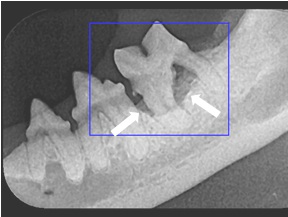

Dog and Cat Abnormal Dental X-rays

X-Rays on Right -- Tooth supporting bone has eroded away from tooth root (white arrows).  Tooth must be removed